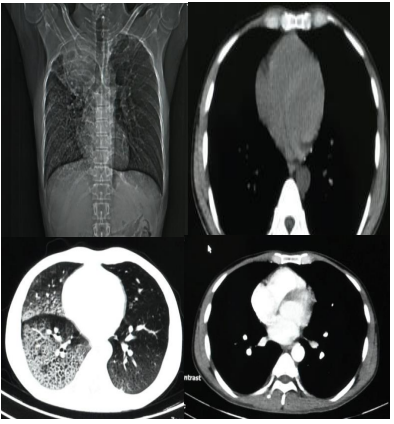

One Stop Service, Deteksi Dini Kanker Paru di RSUP Persahabatan

Direktur utama RSUP Persahabatan, Prof. dr. Agus Dwi Susanto, mengatakan sebagai rumah sakit rujukan respirasi nasional, RSUP Persahabatan menyediakan layanan One Stop Service, deteksi dini kanker paru.

Pelayanan ini didukung oleh kolaborasi antar unit kerja yang ada di RSUP Persahabatan yang dapat memudahkan pasien. Fasilitas deteksi dini MCU untuk kanker paru RSUP Persahabatan antara lain :

1. Dokter spesialis dan sub spesialis paru di bidang onkologi thorax.

2. Peralatan rontgen thorax, CT scan.

3. Laboratorium lengkap dan canggih dalam pelayanan One Stop Service termasuk penanda tumor (tumor marker) dan pemeriksaan biomolekuler.

4. Konsultasi hasil MCU.